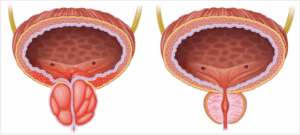

1. The size of the prostate: There are different treatment options that can be offered depending on whether the prostate is relatively small or very large2. The shape of the prostate: Every prostate have two lateral lobes. However, some men develop an additional median lobe that protrudes into the bladder and may increase the complexity of a given procedure.